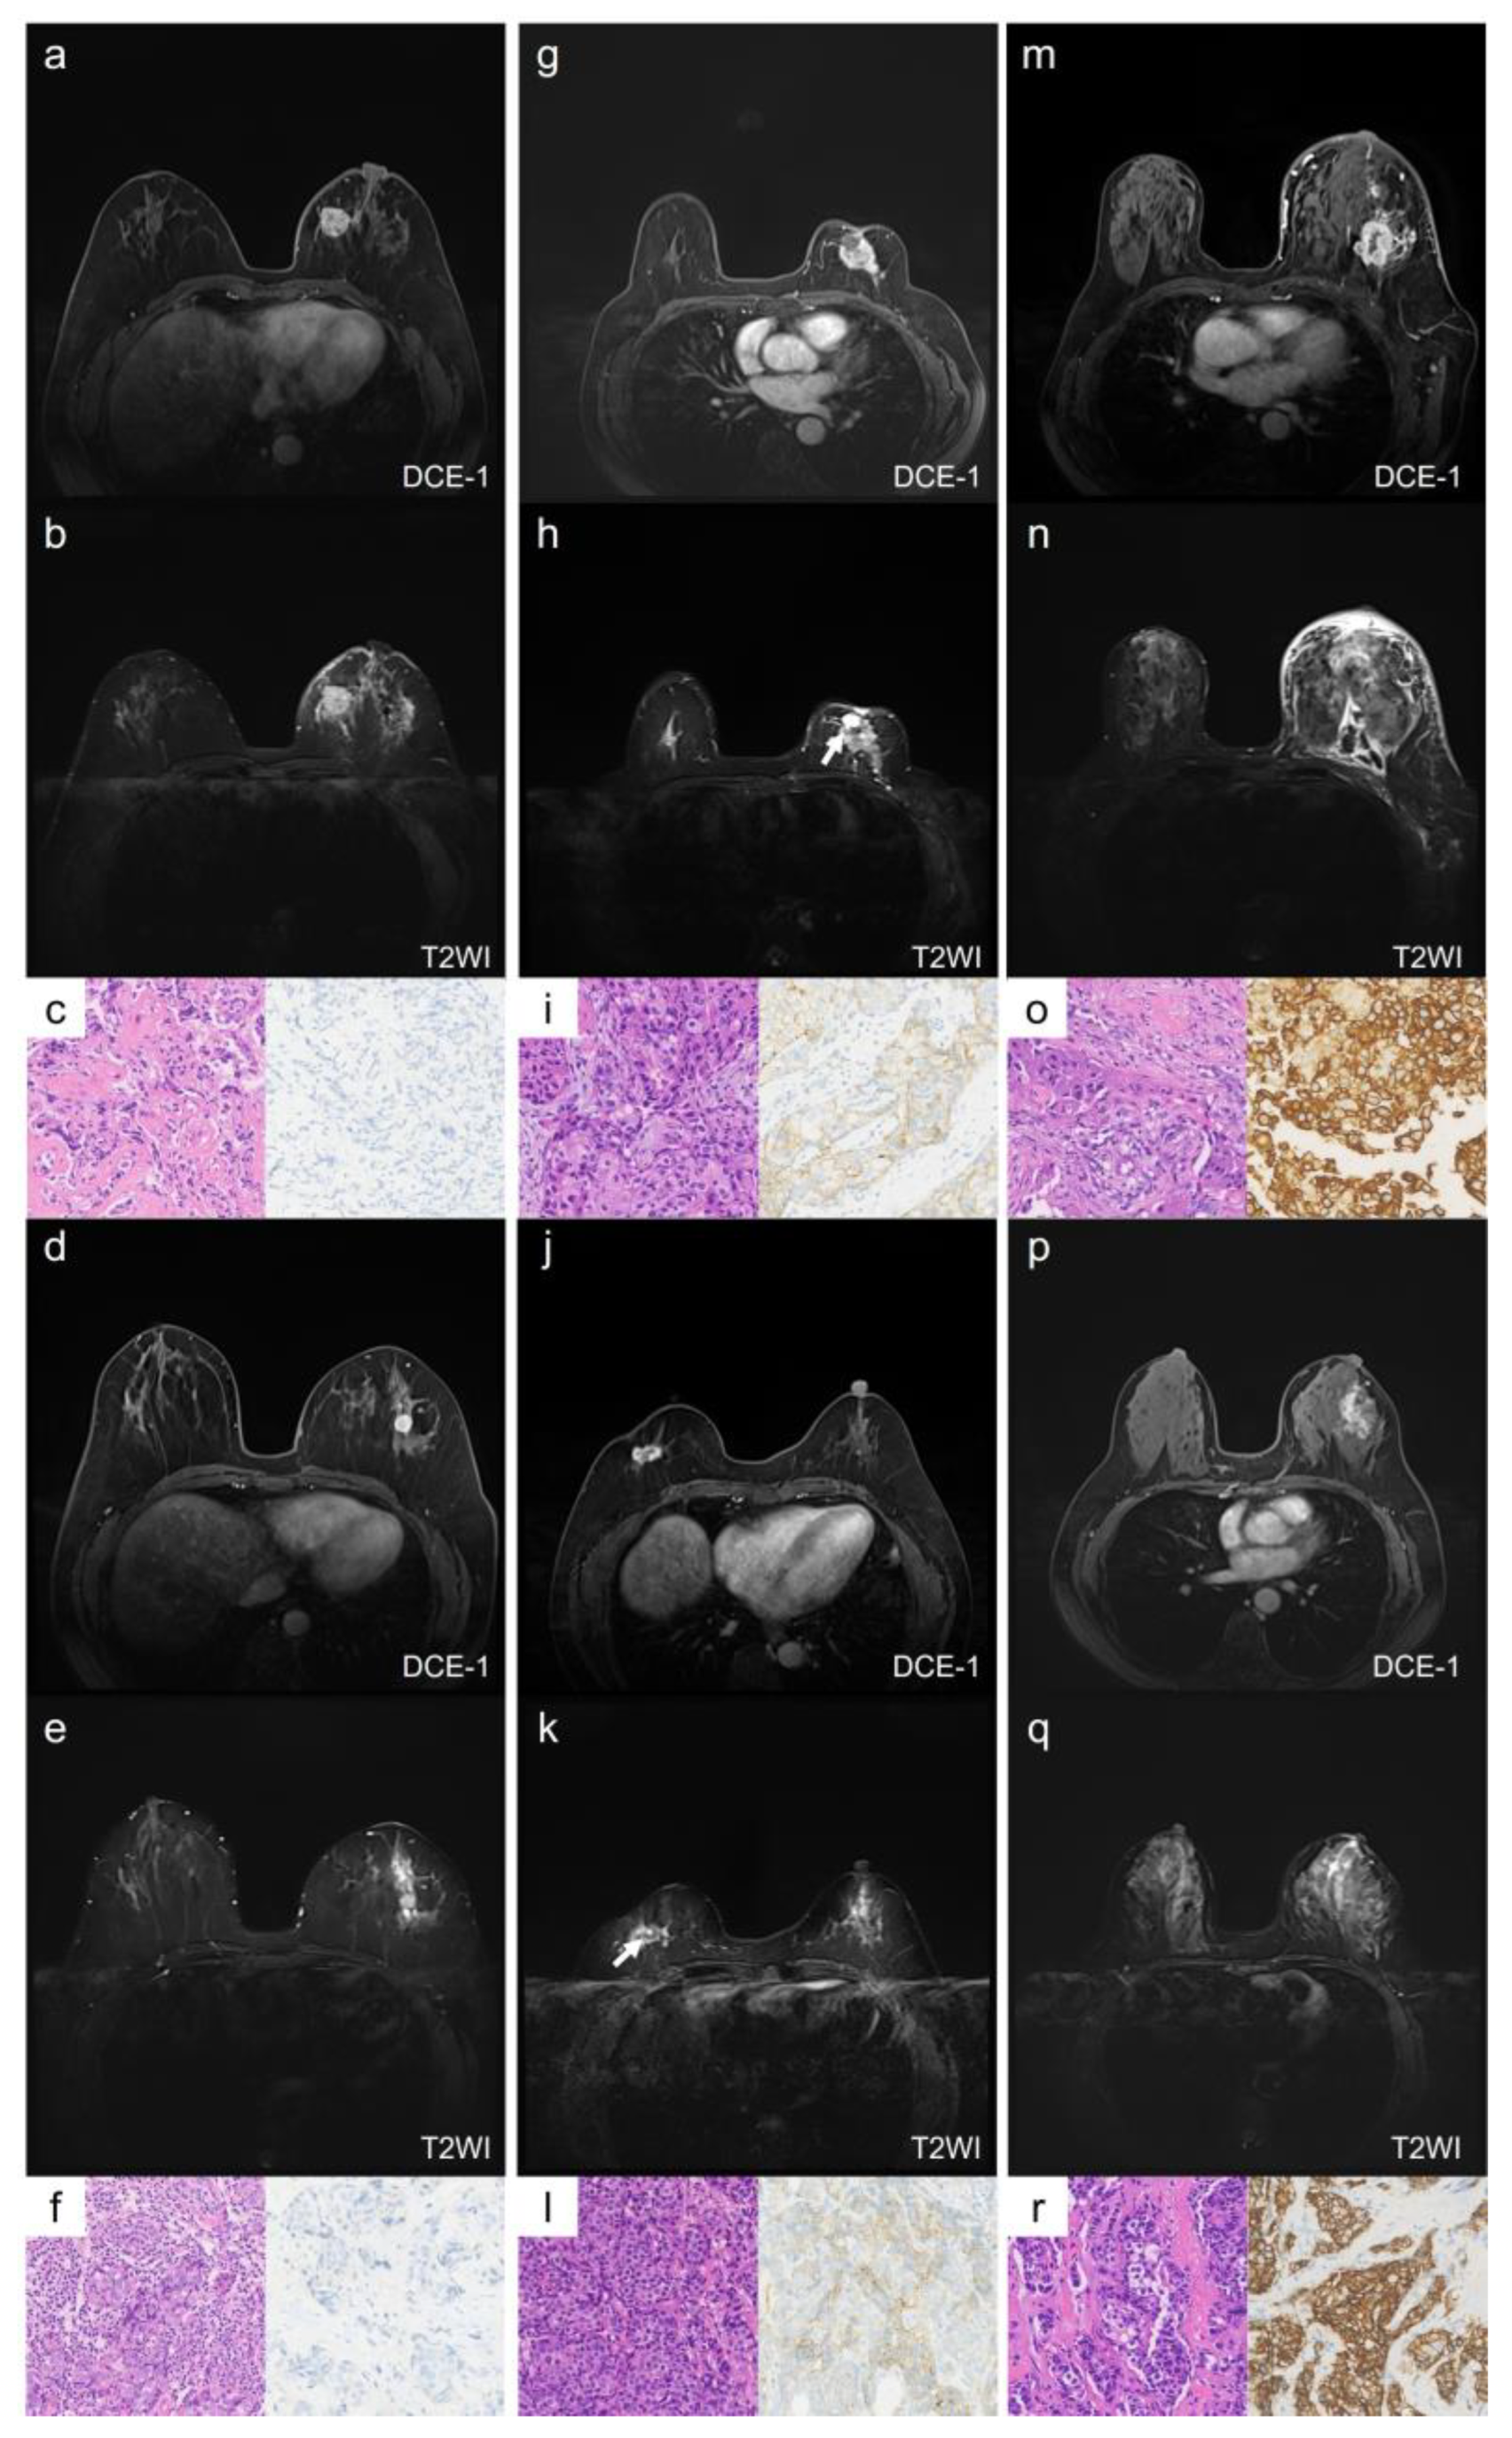

In multivariate analysis, the qualitative MRI features with a p-value < 0.1 from the univariate analysis—intratumoral T2 hyperintensity, mass shape, and mass margin—were included (Table S2). The results showed that irregular shape remained an independent predictor of HER2-low breast cancer when compared with HER2-zero (odds ratio [OR] = 3.91, 95% confidence interval [CI]: 1.38–11.05, p = 0.010) and HER2-overexpression (OR = 2.23, 95% CI: 1.29–8.10, p = 0.012). The AUC for distinguishing HER2-low from HER2-zero was 0.763 (95% CI: 0.667–0.859), and for HER2-low from HER2-overexpression, the AUC was 0.663 (95% CI: 0.550–0.775). Representative cases of the qualitative MRI features for HER2-zero, HER2-low, and HER2-overexpression are illustrated in Figure 2.

Figure 2.

Representative images of qualitative MRI features in HER2-zero, HER2-low, and HER2-overexpression breast cancer. Case 1 (a–c) and Case 2 (d–f) show HER2-zero breast cancer, Case 3 (g–i) and Case 4 (j–l) show HER2-low breast cancer, and Case 5 (m–o) and Case 6 (p–r) show HER2-overexpression breast cancer. Case 1 (a–c): A 59-year-old female with HER2-zero expression breast cancer. The lesion is located in the left breast, has a rounded shape with circumscribed margins, and shows no NME (a). There is no intratumoral hyperintensity on T2WI (b). The HE staining image (×20, (c) left) shows invasive ductal carcinoma, and the IHC result (×20, (c) right) shows an HER2 score of 0. Case 2 (d–f): A 51-year-old female with HER2-zero expression breast cancer. The lesion is located in the left breast, has a rounded shape with circumscribed margins, and shows no NME (d). There is no intratumoral hyperintensity on T2WI (e). The HE staining image (×20, (f) left) shows invasive ductal carcinoma, and the IHC result (×20, (f) right) shows an HER2 score of 0. Case 3 (g–i): A 67-year-old female with low-HER2-expression breast cancer. The lesion is located in the left breast, has an irregular shape and uncircumscribed margins, and shows no NME (g). There is an intratumoral hyperintensity area (arrow) on T2WI (h). The HE staining image (×20, (i) left) shows invasive ductal carcinoma, and the IHC result (×20, (i) right) shows an HER2 score of 1+. Case 4 (j–l): A 59-year-old female with low-HER2-expression breast cancer. The lesion is located in the right breast, has an irregular shape and uncircumscribed margins, and shows no NME (j). There is an intratumoral hyperintensity area (arrow) on T2WI (k). The HE staining image (×20, (l) left) shows invasive ductal carcinoma, and the IHC result (×20, (l) left right) shows an HER2 score of 1+. Case 5 (m–o): A 61-year-old female with HER2-overexpression breast cancer. The lesion is located in the left breast, has an irregular shape and uncircumscribed margins, and shows NME (m). There is no intratumoral hyperintensity on T2WI (n). The HE staining image (×20, (o) left) shows invasive ductal carcinoma, and the IHC result (×20, (o) right) shows an HER2 score of 3+. Case 6 (p–r): A 55-year-old female with HER2-overexpression breast cancer. The lesion is located in the left breast, and shows as an NME lesion (p). There is no intratumoral hyperintensity on T2WI (q). The HE staining image (×20, (r) left) shows invasive ductal carcinoma, and the IHC result (×20, (r) right) shows an HER2 score of 3+. NME: non-mass enhancement; DCE-1: enhancement during the first phase.